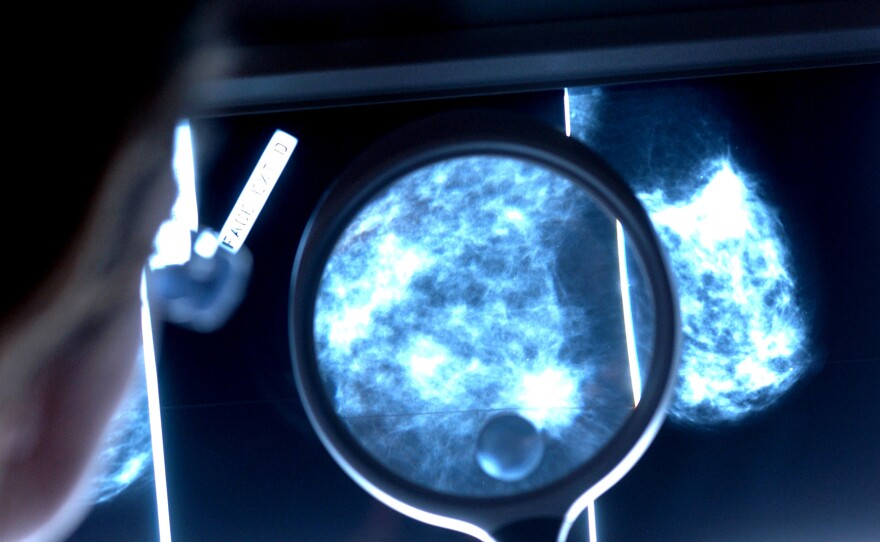

When do women get the most benefit from mammograms to find breast cancer?

Phanie Science Source